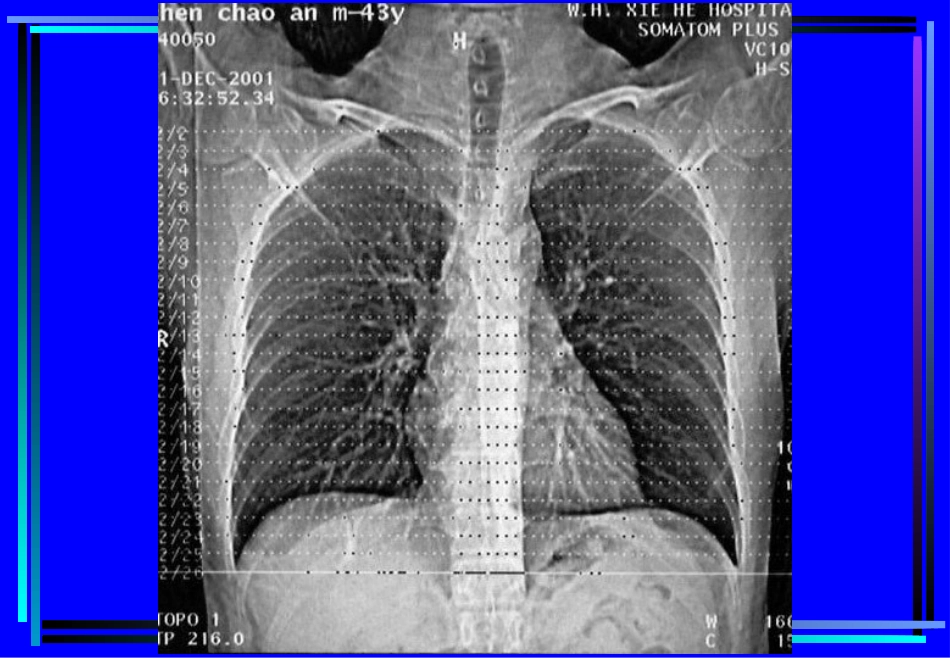

胸部CT诊断第一节胸部CT检查一、胸部CT扫描方法(一)普通扫描(平扫plainCTscan)(二)增强扫描(contrastenhancement,CE)1.注药方法团注法(bolusinjection)静滴法2.扫描程序静态CT扫描动态CT扫描(dynamicCTscan)(三)特殊扫描1.薄层扫描2.高分辨率CT扫描(HighresolutionCT,HRCT)3.CT血管造影(CTangiography,CTA)4.心电门控扫描二、CT对胸部疾病的诊断价值与限度(一)诊断价值1.肺部小病灶与早期病变2.咯血查因3.肺不张、肺实变4.肺肿瘤分期5.肺弥漫性病变6.肺气肿的诊断及功能评价7.肺血管性病变8.胸水查因(二)影响CT检出与诊断的因素(主要为常规CT)1.运动伪影2.部分容积效应3.层厚与层间距4.大量胸水5.一病多像,一像多病三、胸部正常CT解剖(一)窗技术1.纵隔窗:窗位30-60Hu,窗宽300-500Hu2.肺窗:窗位-700~-400Hu,窗宽1000-1500Hu(二)纵隔(mediastinum)(三)肺(lung)第二节肺部疾病的CT诊断一、先天性疾病1.肺隔离症(pulmonarysequestration)某一肺段和正常肺组织及气管和支气管树相互分离,无呼吸功能,血供来自主动脉系统,分叶内型和叶外型两类。CT表现:部位:两下肺、脊柱旁。形态:囊实性或囊性或实性,邻近肺野斑片状影。血供:体循环,病灶内血管异常。鉴别诊断:支气管源性囊肿、肺脓肿、先天性膈疝。2.支气管囊肿(bronchogeniccyst)为支气管的先天发育异常,根据组织学来源可分为支气管囊肿和支气管肺囊肿(pulmonarybronchogeniccyst)。CT表现:部位:纵隔与肺的任何部位,多见于气管隆突5cm范围内。形态:圆形、椭圆形、边缘锐利,壁菲薄。密度:均匀,可有出血和液气平,壁可强化。二、支气管扩张症(bronchiectasis)病因:先天性或后天性病理:肉眼观,支气管呈柱状、囊状、静脉曲张状或混合状扩张。镜下观,粘膜柱状上皮呈急、慢性炎性改变,伴弹力纤维、平滑肌和软骨的损害。CT表现:病变支气管壁增厚,管腔扩大,形态多样。1.柱状扩张:“双轨”征、“印戒”征。2.囊状扩张:葡萄串状、卷发样。3.曲张形扩张:粗细不均的囊柱状。4.混合型合并粘液栓时,腔内可见棒状或结节状软组织密度影,咳痰后可消失,同时可见肺野内出血,继发感染等征象。三、肺感染性病变1.支气管肺炎支气管肺炎(bronchopneumonia)或小叶性肺炎(lobularpneumonia)病理:小支气管壁充血、水肿、间质炎性细胞浸润,小叶渗出、实变、气肿或不张。CT表现:两肺中下野中内带,支气管血管束增粗,沿其分布小斑片影及边缘模糊的小结节影。2.大叶性肺炎大叶性肺炎(lobarpneumonia),炎症累及整个肺叶,或呈肺段分布。病理:充血期,毛细血管充血,肺泡内可有少量浆液性渗出。红色肝样变期,渗出液中含较多红细胞。灰色肝样变期,渗出液中含大量白细胞。消散期,渗出液溶解、吸收。CT表现:渗出期表现为磨玻璃样影;实变期呈叶、段的实变,可见空气支气管征,叶间裂可向外膨出;消散期则呈斑片状影。鉴别诊断:阻塞性肺炎,结核性大叶炎、肺肿瘤(腺癌、肺泡癌或淋巴瘤)。3.肺脓肿肺脓肿(lungabscess),由化脓性细菌引起的肺坏死性炎性病变,分急性和慢性肺脓肿。病理:细支气管阻塞,小血管炎性栓塞,肺组织坏死、液化,周围有纤维组织增生。CT表现:急性期:大片密实影,中心密度较低,空洞形成后,壁厚而模糊,内有液平;慢性期:洞壁清晰,内壁多不规整,增强扫描洞壁强化,支气管、肺血管于脓肿边缘截断。鉴别诊断:结核空洞、癌性空洞4.肺结核肺结核(pulmonarytuberculosis),由人型或牛型结核杆菌引起的肺部慢性传染病。病理:渗出-结核性肺泡炎,增殖-结核性结节肉芽肿。继发改变:干酪样坏死、液化、空洞、播散;纤维化、钙化。CT表现:Ⅰ型:原发性肺结核(primarytuberculosis)纵隔、肺门淋巴结增大,增强扫描多呈环形强化。肺内原发灶呈片影或段、叶的实变,内可见低密度坏死、空洞。可合并叶或段的不张。Ⅱ型:血行播散型肺结核(acutemiliarytuberculosisandchronicdisseminatedtuberculosis)急性血行播散型,CT表现为双肺广泛分布的1-2mm小点状阴影,密度均匀,边界清,分布均匀,与支气管走行无关,以HRCT显示为佳。亚急性或慢性血...